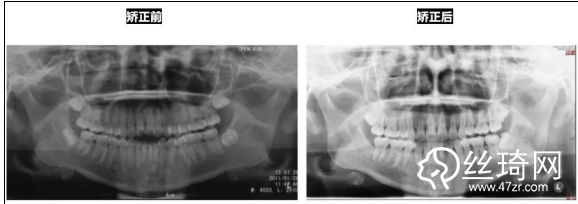

* 影像學(xué)檢查分析(以及調(diào)節(jié)前后影像對比):

全景片: